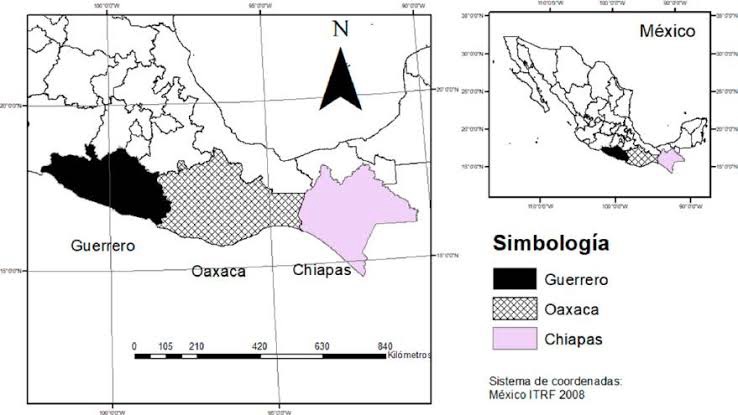

Confirman dos casos humanos de miasis por gusano barrenador en Chiapas; Oaxaca en alerta sanitaria

SSO: 1°caso en humanos de miasis por gusano barrenador en Chiapas

La Secretaría de Salud ha confirmado dos casos de miasis humana causada por el gusano barrenador (Cochliomyia hominivorax) en el estado de Chiapas. Hasta la fecha, no se han reportado contagios en personas en Oaxaca, aunque las autoridades sanitarias mantienen una vigilancia epidemiológica activa en la región. Casos confirmados en Chiapas El primer caso se […]